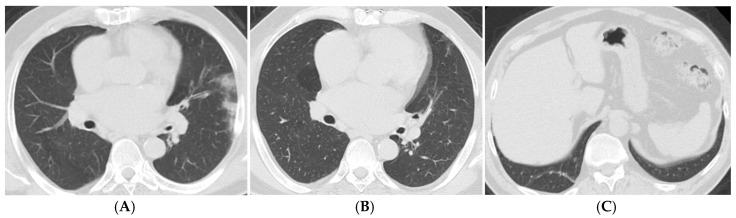

Background: This study aims to systematically evaluate the findings from computed tomography (CT) examinations conducted at least three months post-diagnosis of COVID-19 in patients diagnosed between 2020 and 2024. Objective: To determine the frequency and characteristics of CT findings in the post-COVID-19 period, analyze long-term effects on lung parenchyma, and contribute to the development of clinical follow-up and treatment strategies based on the collected data. Materials and Methods: Ethical approval was obtained for this retrospective study, and individual consent was waived. A total of 76 patients were included in the study, aged 18 and older, diagnosed with COVID-19 between March 2020 and November 2024, who underwent follow-up chest CT scans at 3-6 months, 6-12 months, and/or 12 months post-diagnosis. CT images were obtained in the supine position without contrast and evaluated by two experienced radiologists using a CT severity score (CT-SS) system, which quantifies lung involvement. Statistical analyses were performed using IBM SPSS 23.0, with significance set at p < 0.05. Results: The results indicated a mean CT-SS of 10.58 ± 0.659. Significant associations were found between age, CT scores, and the necessity for intensive care or mechanical ventilation. The most common CT findings included ground-glass opacities, reticular patterns, and traction bronchiectasis, particularly increasing with age and over time. Conclusion: This study emphasizes the persistent alterations in lung parenchyma following COVID-19, highlighting the importance of continuous monitoring and tailored treatment strategies for affected patients to improve long-term outcomes.

Abstract Image